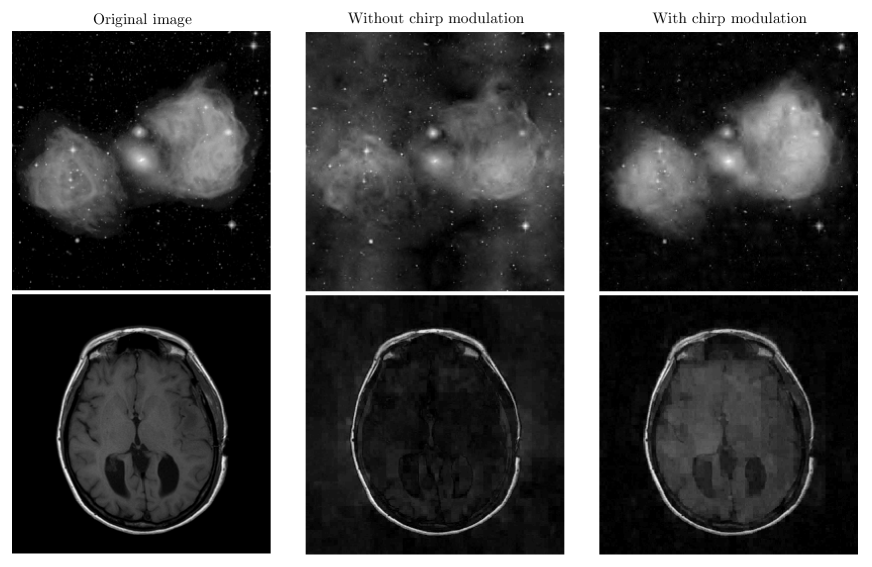

Up to the introduction of the matrix and the substitution of the linear chirp modulation for the random modulation, we are in the same setting as the one studied in Section 2. To illustrate the effectiveness of the spread spectrum technique, we consider two images of size showed in Figure 3. The first image shows the radio emission associated with the encounter of a galaxy with its northern neighbor. It was acquired with the Very Large Array in New Mexico [49]. The second image shows a brain acquired in an MRI scanner. This image is part of the Brainix database [50]. These images are probed according to relation (12) in the absence () and presence () of a linear chirp modulation. Independent and identically distributed Gaussian noise with zero-mean is also added to the measurements. The variance of the noise is defined such that the input is ( stands for the sampled standard deviation of ). The images are reconstructed from complex Fourier measurements by solving the -minimization problem (5). Note that in order to stay in the setting of the theorems presented so far, no reality constraint is enforced in the reconstructions, so that the reconstructed images are complex valued. The sparsity bases used are the Daubechies-6 and Haar wavelet bases for the galaxy and the brain respectively. In each case, reconstructions are performed for different noise and mask realizations. The complex magnitudes of reconstructed images with median mean squared errors are presented in Figure 3.

In the absence of linear chirp modulation, the quality of the reconstructed image is very low. However, one can already note that the fine scale structures are much better reconstructed than those at large scales. The fine details live at the small scales of the wavelet decomposition whereas the large structures live at larger scales. The small scale wavelets being more incoherent with the Fourier basis than the larger wavelets, the high frequency details are naturally better recovered.

In the presence of the linear chirp modulation, all the wavelets in become optimally incoherent with the Fourier basis thanks to the universality of the spread spectrum technique. Consequently, as one can observe on Figure 3, the low and high frequency details are better reconstructed and the image quality is drastically enhanced. Note that much better reconstructions can be obtained for the brain image by substituting the Total Variation norm333 norm of the magnitude of the gradient. for the norm in (5) [13, 30]. However, Theorems 1 and 3 do not hold for such a norm.

Let us acknowledge that these simulations are not fully realistic. For example, in radio-interferometry, the spatial frequency cannot be chosen at random. To simulate realistic acquisitions, one would have to consider non-random measurements in the continuous Fourier plane. Such a study is beyond the scope of this work. However, in the context of MRI, part of the authors implemented and tested this technique on a real scanner with in vivo acquisitions [29, 30].